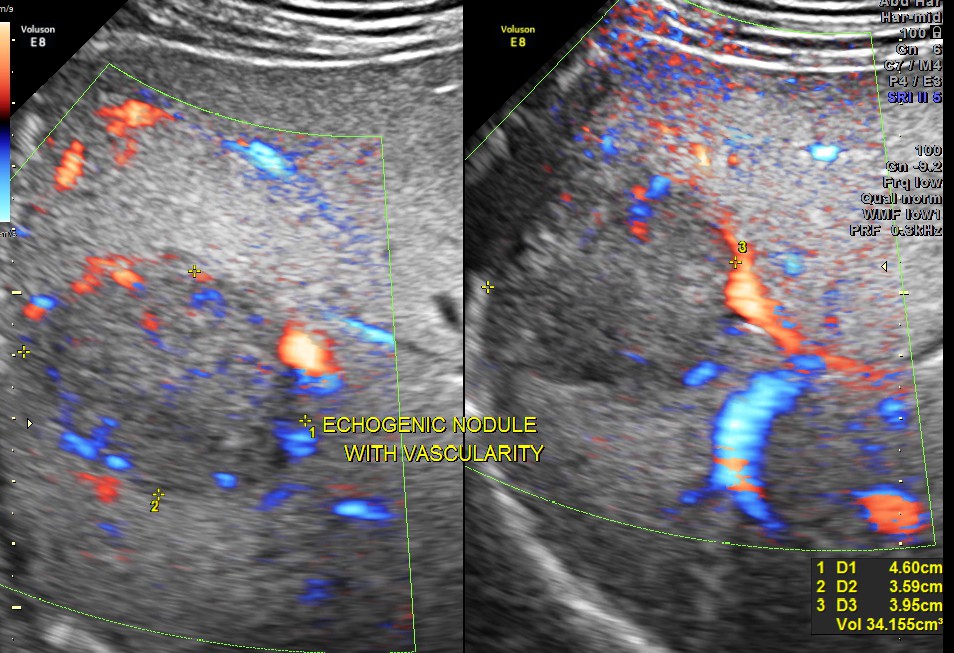

An echogenic nodule with vascularity is seen.